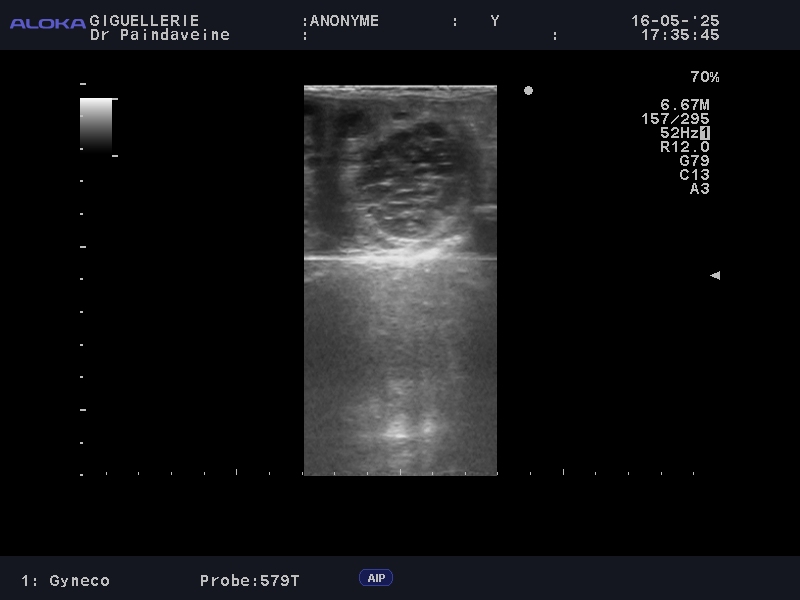

Le praticien réalise une évaluation clinique et échographique complète, portée sur les structures clés :

• Ovaires : Suivi de la dynamique folliculaire pour prédire l’ovulation et détecter d'éventuelles anomalies fonctionnelles (corps jaunes persistants, kystes).

• Utérus : Contrôle de la tonicité et de la vacuité utérine. Nous portons une attention particulière à l'absence d'œdème post-ovulatoire excessif ou d'endométrite, facteurs majeurs d'échecs précoces.

Si l’insémination en semence fraîche ou réfrigérée offre une certaine souplesse, le recours à la semence congelée (IAC) exige une précision chirurgicale. La survie des spermatozoïdes cryoconservés étant réduite, le suivi devient intensif pour garantir un dépôt de semence au plus proche de l'ovulation.